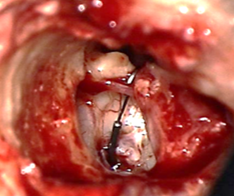

![]() |

Figura 1. Foco otoesclerótico |

La otosclerosis es una enfermedad que afecta la cápsula ótica, caracterizada por una remodelación ósea anormal. Este proceso de remodelación, que ocurre de manera natural en todos los huesos del cuerpo, implica un delicado equilibrio entre la resorción ósea mediada por los osteoclastos y la formación ósea realizada por los osteoblastos. En la otosclerosis, esta alteración a menudo resulta en una fijación parcial del estribo, particularmente en la porción anterior de la ventana oval, específicamente en la fissula antefenestran (ver Fig. 1).